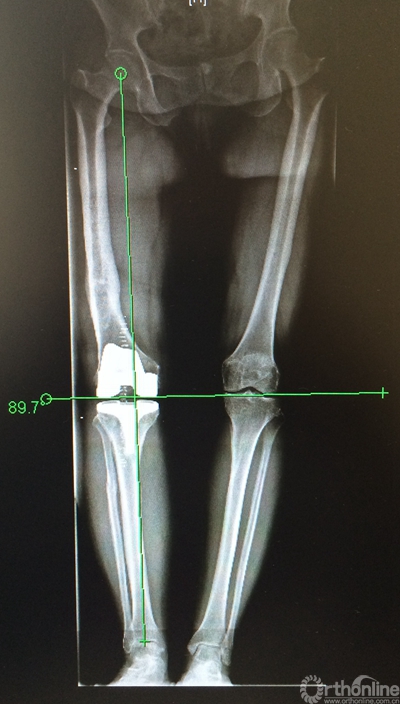

2.4 术后处理

术后常规进行抗凝、预防感染、镇痛处理,24小时拔除引流后关节伸屈功能锻炼,并扶拐下地负重。拍摄术后X片,下肢力线恢复,假体安放位置准确(见图5)。

图5.术后全长片显示下肢力线恢复良好。